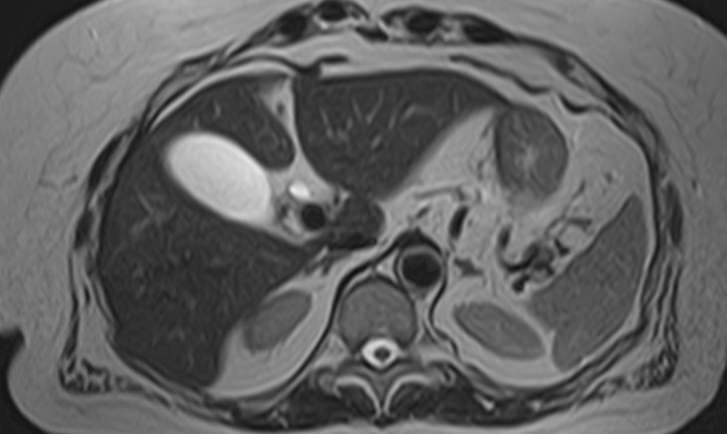

В клинике «Доступная медицина» МР томография проводится на новейшем высокопольном томографе экспертного класса TOSHIBA VANTAGE TITAN 1,5 Тесла. Высокая индукция магнитного поля обеспечивает повышенную четкость изображений при проведении обзорной МРТ брюшной полости, что гарантирует точность и эффективность диагностики заболеваний печени, желчного пузыря, поджелудочной железы и селезенки. Аппарат послойно сканирует исследуемую область с шагом от 1 мм в различных плоскостях, затем трансформирует результаты в трехмерные изображения превосходного качества. Для уточнения характера патологических изменений одного из органов назначается прицельная МР томография данного органа.

Для расширения возможностей диагностики, при необходимости уточнения характера патологических изменений применяется контрастное усиление. Для этого в вену вводится контрастный препарат, содержащий металл гадолиний (Магневист, Гадовист и др). Препарат фиксируется в очагах поражения, позволяя диагностировать их при минимальных размерах, что бывает особенно важно в диагностике опухолей.

- Доброкачественные образования (кисты, гемангиомы) и злокачественные опухоли органов брюшной полости (первичные опухолевые очаги и метастатические поражения, в том числе, брюшины).

- Заболевания печени (жировая инфильтрация печени, гепатиты, цирроз и др).

- Заболевания желчного пузыря и желчевыводящих протоков, поджелудочной железы (желчекаменная болезнь, холецистит, панкреатит и др).